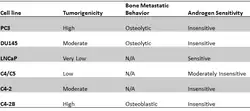

PC3 cells have high metastatic potential compared to other pancreatic cells of DU145 cells, which have a moderate metastatic potential, and to LNCaP cells, which have low metastatic potential. Comparisons of the protein expression of PC3, LNCaP, and other cells have shown that PC3 is characteristic of small cell neuroendocrine carcinoma.[4]